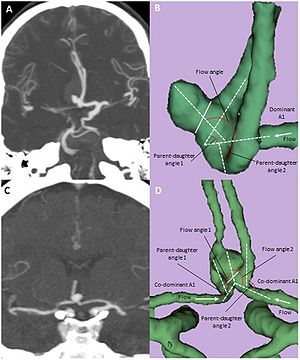

Association Between Vascular Anatomy and Posterior Communicating Artery Aneurysms

Publication: World Neurosurg. 2015 Nov;84(5):1251-5. PMID: 26074436 Authors: Can A, Ho AL, Emmer BJ, Dammers R, Dirven CM, Du R. Institution: Department of Neurosurgery, Brigham and Women's Hospital, Harvard Medical School, Boston, MA, USA. Background/Purpose: Hemodynamic stress, conditioned by the geometry and morphology of the vessel trees, plays an important role in the formation of intracranial aneurysms. The aim of this study was to identify image-based location-specific morphologic parameters that are associated with posterior communicating artery (PCoA) aneurysms. Methods: Morphologic parameters obtained from computed tomography angiography of 56 patients with PCoA aneurysms and 23 control patients were evaluated with 3D Slicer, an open-source image analysis software, to generate 3-dimensional models of the aneurysms and surrounding vasculature. Segment lengths, diameters, and vessel-to-vessel angles were examined. To control for genetic and clinical risk factors, the unaffected contralateral side of patients with unilateral PCoA aneurysms was used as a control group for internal carotid artery (ICA)-related parameters. A separate control group with visible PCoAs and aneurysms elsewhere was used as a control group for PCoA-related parameters. Results: Internal carotid artery-related parameters were not statistically different between the PCoA aneurysm and control groups. Univariate and multivariate subgroup analysis for patients with visualized PCoAs demonstrated that a larger PCoA diameter was significantly associated with the presence of a PCoA aneurysm (odds ratio = 12.1, 95% confidence interval = 1.3-17.1, P = 0.04) after adjusting for other morphologic parameters. Conclusions: Larger PCoA diameters are associated with the presence of PCoA aneurysms. These parameters may provide objective metrics to assess aneurysm formation and growth risk stratification in high-risk patients. |